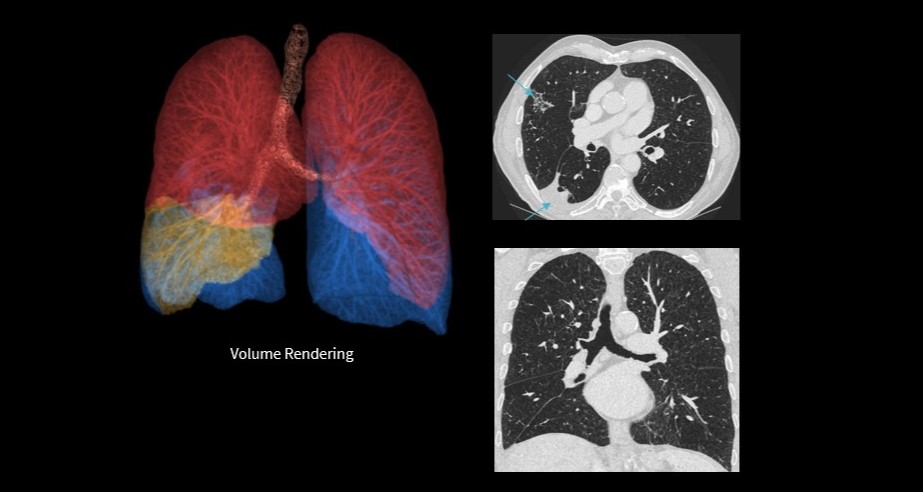

True Definition DL is designed to overcome these limitations by delivering exceptional clarity in high resolution CT imaging for bone and lung without compromising dose efficiency or acquisition speed. Its DL–driven approach enhances spatial resolution across multiple directions, integrates artifact suppression, and supports high definition (HD) mode to improve the visibility of fine anatomical structures such as small airways, pulmonary nodules, and trabecular bone patterns. This enhancement is critical for high-contrast imaging tasks, particularly in bone and lung imaging, where diagnostic confidence hinges on the ability to resolve subtle details.

Additionally, the solution offers a 1024 matrix for high resolution display, and chest imaging achievable in under one second, empowering clinicians to see more, diagnose with greater confidence, and expand access to high resolution imaging performance across a broader range of clinical settings.

“True Definition DL delivers exceptional spatial resolution for visualizing very small anatomical structures,” shares Dr. Stefanie Bitschnau, radiologist and collaborator at Radiomed. “In chest imaging, this level of detail is particularly valuable for assessing small airways, supporting earlier and more confident evaluation of interstitial lung disease. Additionally, the technology is highly beneficial in applications such as inner ear imaging with petrous bone scans, where it allows us to clearly visualize the auditory ossicles and detect erosions at an early stage. This improved definition also supports more confident fracture assessment.”